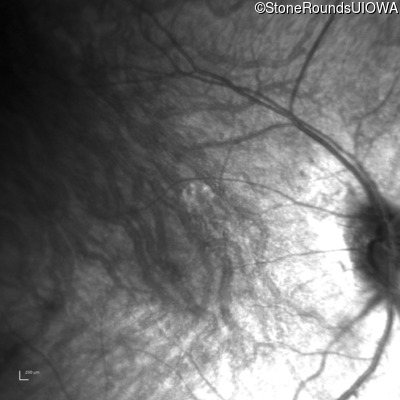

Infrared Fundus Photograph - Right - 10/300 sc

Exemplar